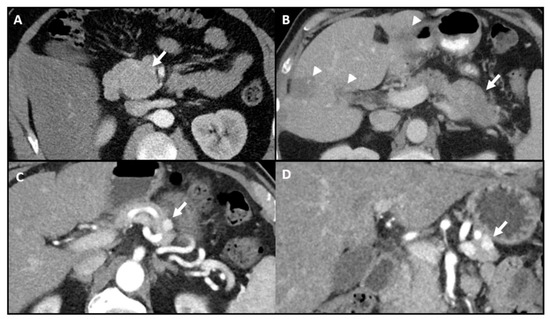

2. Non-Invasive Pre-Operative Localization